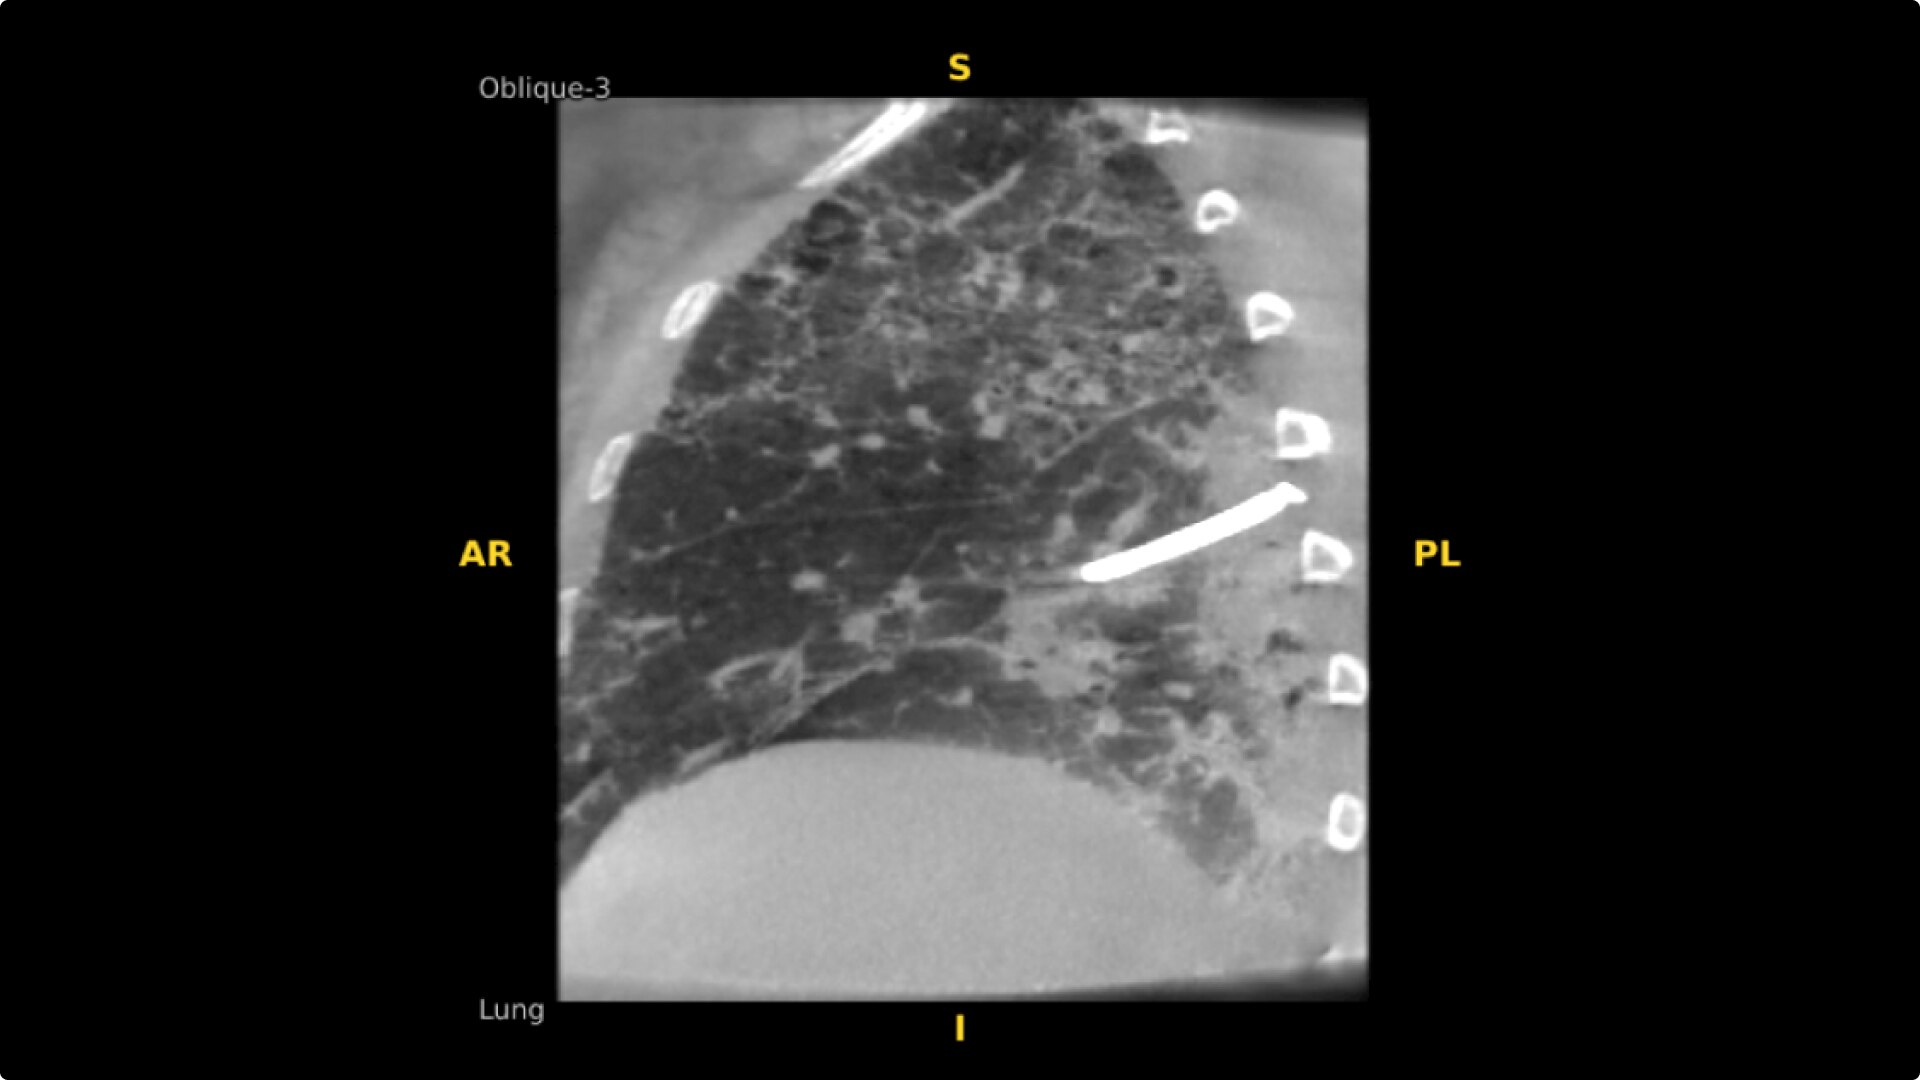

The OEC 3D provides comprehensive imaging with precise 19 cm x 19 cm x 19 cm 3D volumes and exceptional 2D images intraoperatively.

The OEC 3D presents five perspectives: Axial, Coronal, Sagittal, MIP, and VR, on a 4K display for clear and detailed review of 3D volumes and 2D images.

Select Lung Preset for optimized view of pulmonary structures. Easily change slices or adjust slice thickness for multiplanar assessment of lesions and bronchial structures.

Analyze CT-like images with the OEC 3D Volume Viewer which includes Multi Oblique Mode with reference coordinates, Window Level/Window Width, rotate, zoom, and more for quick and comprehensive tool-in-lesion confirmation.